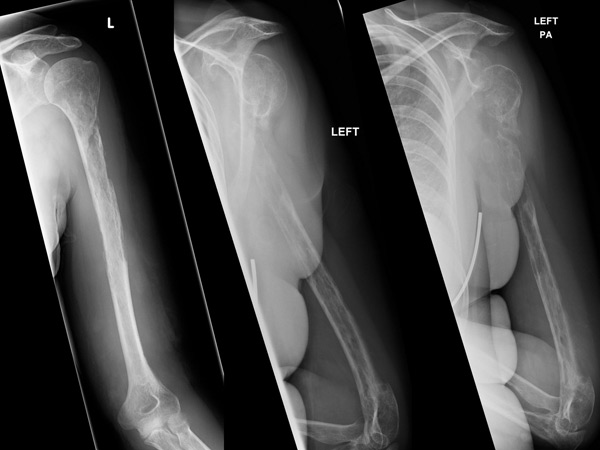

This strange case of a woman's bones disappearing seems to baffle the medics, as the x-ray shows the bones disappearing over a period of time!

It is reported that the 44-year-old woman was previously healthy. She consulted a doctor when she experienced increasing pain in her left shoulder. During the X-ray, medics saw a lesion in her humerus bone, which is the bone in the upper arm. It was assumed to be cancer. But her biopsy results didn't show cancer. After several months, she underwent another biopsy, which revealed a benign blood vessel tumour.

The woman continued to have pain and swelling in her arm for several months. Her bone apparently started getting fractured from just minor injuries. About 18 months when the doctors went through all the scans over the period of time, the doctors realised that her bones were vanishing! Both her humerus and her ulnar bone seemed to be disappearing on the X-ray report. The reports also showed that blood vessel growths were replacing her bone tissue.